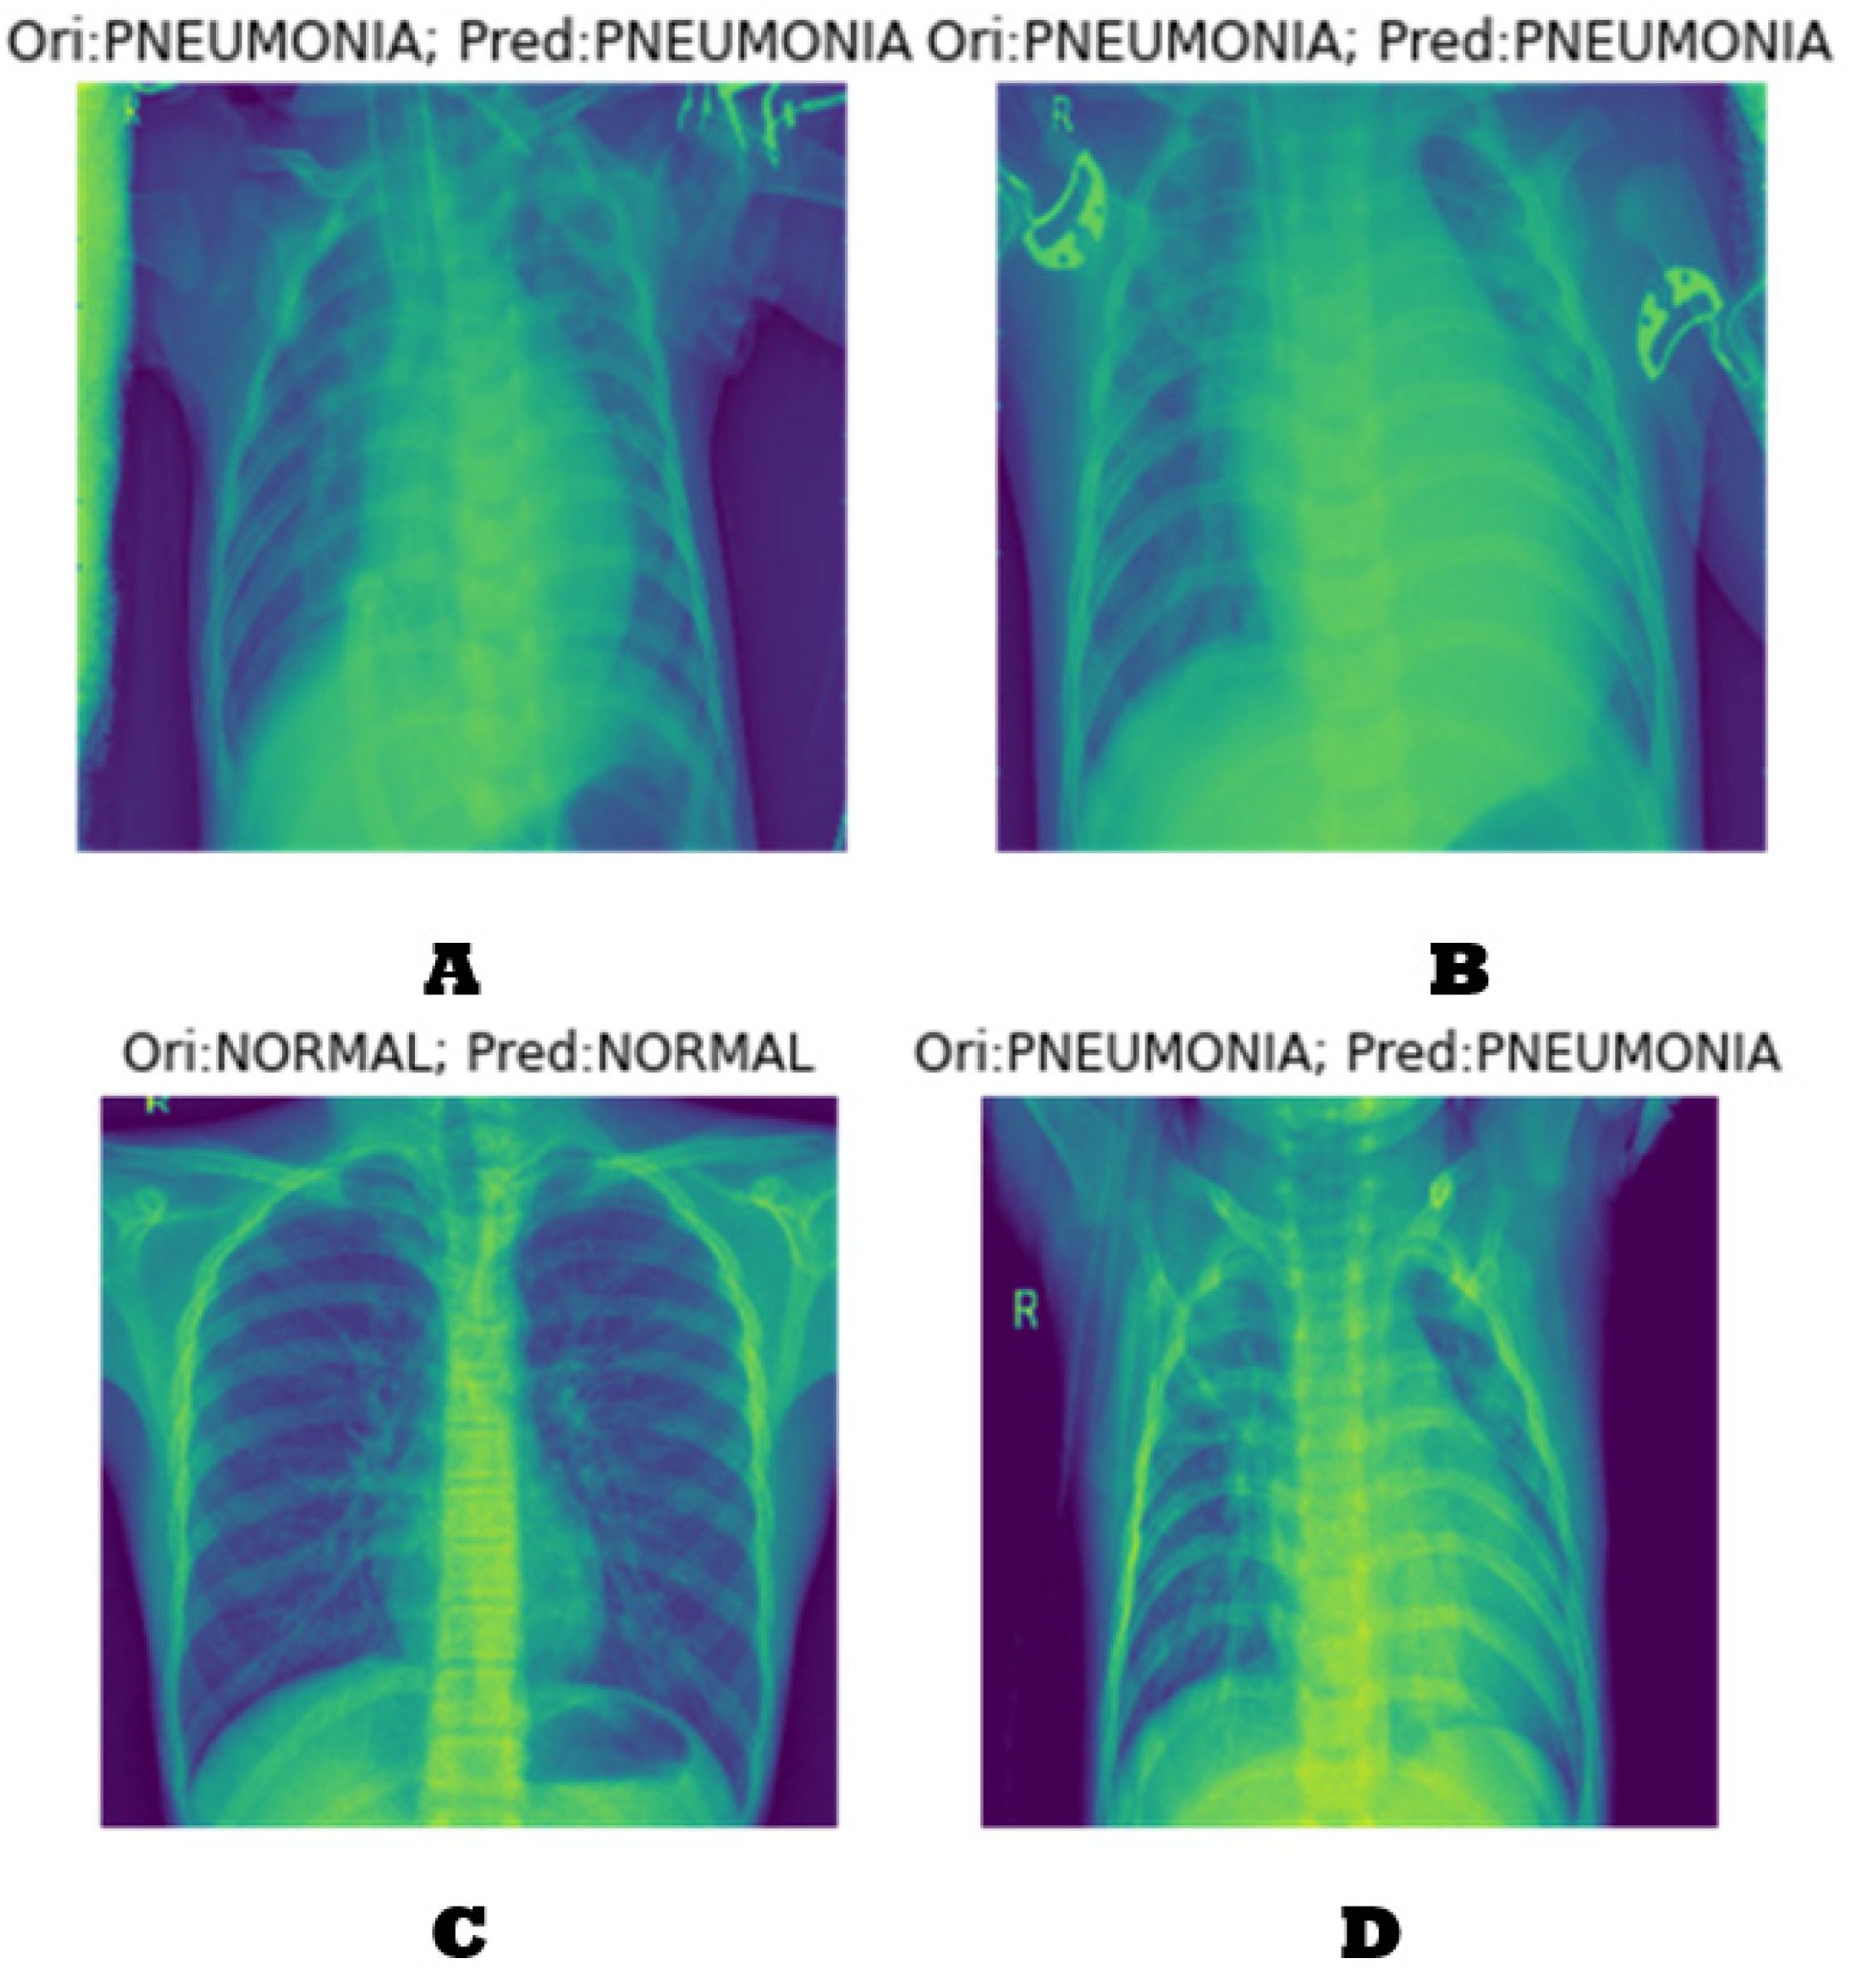

4.1. Generating the DCGAN Image

- Part 1: the discriminator is trained to maximize the probability of correctly classifying the given input as either real or fake.

- Part 2: the generator is trained by minimizing log (1-D(G-(Z))) to generate a better fake image.